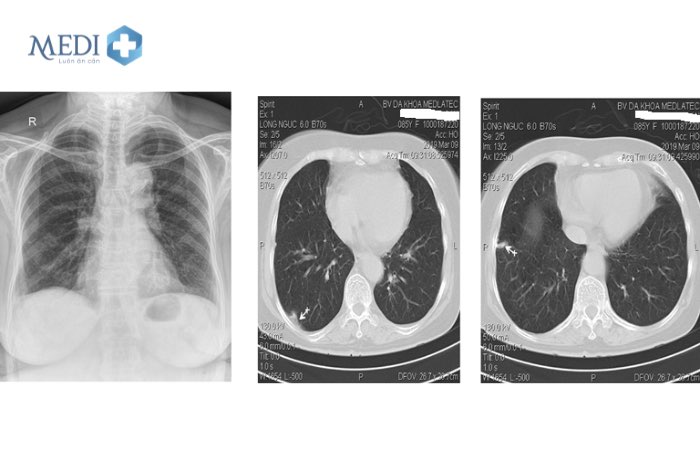

Chụp X-quang phổi

Đây là phương pháp giúp phát hiện các khối u trong phổi qua hình ảnh chụp chiếu. Ưu điểm của phương pháp này là có thể nhìn rõ các khối u ở cả các kích thước rất nhỏ. Tuy nhiên do hình chụp X-quang chỉ thể hiện màu sắc xám trắng nên không thể dựa vào đó để kết luận u lành hay u ác tính. Do đó sẽ cần can thiệp các phương pháp khác để chẩn đoán chính xác hơn.

Chụp cắt lớp vi tính (CT) lồng ngực liều thấp

Chụp CT là phương pháp chẩn đoán hình ảnh thường được sử dụng khi chẩn đoán ung thư phổi. Với phương pháp chụp cắt lớp vi tính lồng ngực liều thấp, có những lợi ích sau:

• Các nốt nhỏ < 10mm nghi ngờ là khối u phổi

• Thời gian chụp nhanh hơn phương pháp bình thường, phù hợp với bệnh nhân có triệu chứng khó thở

• Không cần tiêm thuốc cản quang nên phù hợp với những bệnh nhân có dị ứng với thuốc, không xâm lấn nên không gây đau đớn

• Mức độ phơi nhiễm tia X ít hơn phương pháp chuẩn 90%

Phương pháp này được khuyến khích cho những đối tượng có nguy cơ mắc ung thư phổi cao, với tần suất mỗi năm một lần để kịp thời phát hiện các dấu hiệu bệnh từ sớm.